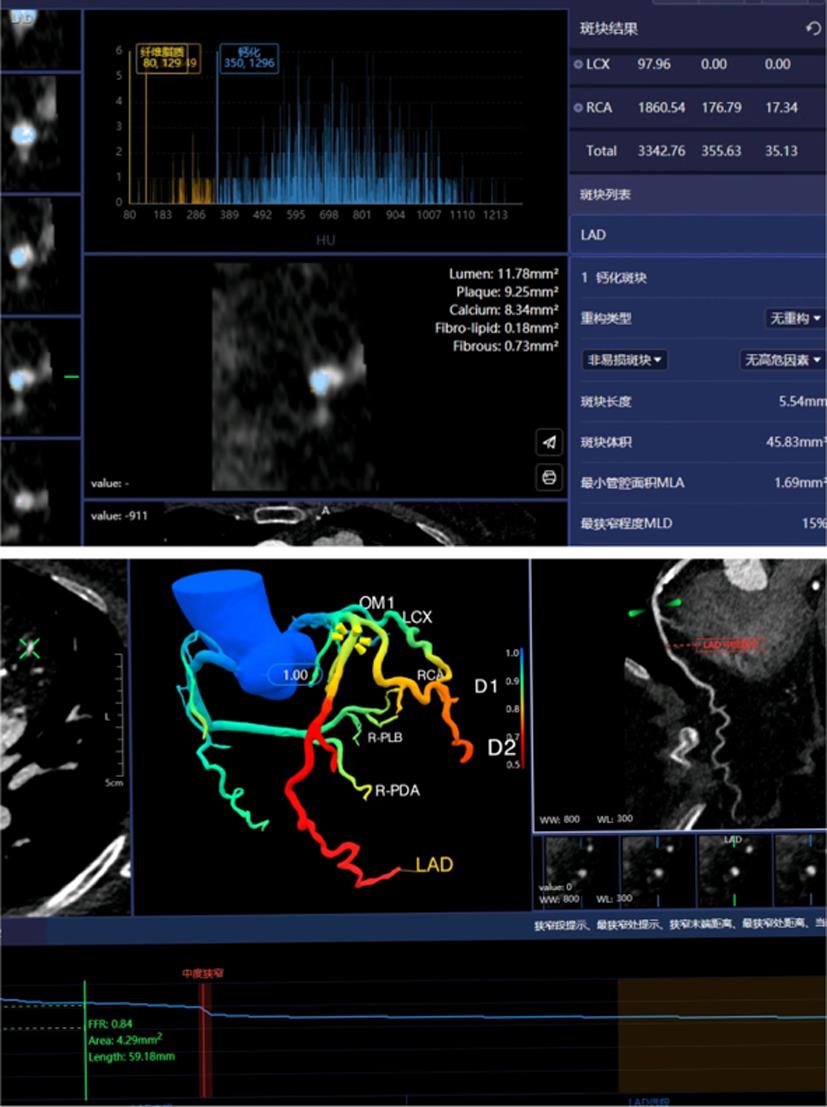

张晓蕾, 唐春香, 李建华, 等. 冠状动脉CTA: 斑块特征定量参数与血流储备分数的相关性分析[J]. 放射学实践, 2018, 33(12): 1261-1265.

庞智英, 杨飞, 苏亚英, 等. 冠状动脉CT血管成像联合基于CT的血流储备分数预测阻塞性冠心病主要不良心脏事件的价值[J]. 实用医学杂志, 2021, 37(20): 2675-2680.

李苏豫, 唐春香, 张龙江. 冠状动脉CT血管成像评估易损斑块新进展[J]. 中华放射学杂志, 2022, 56(3): 330-334.

ZHUANG B, WANG S, ZHAO S, et al. Computed tomography angiography-derived fractional flow reserve (CT-FFR) for the detection of myocardial ischemia with invasive fractional flow reserve as reference: systematic review and meta-analysis[J]. Eur Radiol, 2020, 30(2): 712-725.

QIAO H Y, WU Y, LI H C, et al. Role of Quantitative Plaque Analysis and Fractional Flow Reserve Derived From Coronary Computed Tomography Angiography to Assess Plaque Progression[J]. J Thorac Imaging, 2023, 38(3): 186-193.

宋瑶,霍怀璧,李晗,等. 冠状动脉CTA多参数AI特征对急性冠脉综合征的诊断价值[J]. 放射学实践, 2023, 38(7): 873-878.

南丽虹, 李睿君, 冯进堂, 等. 基于CT血管成像的斑块定量分析在冠状动脉血流动力学异常诊断中的应用价值[J]. 中华解剖与临床杂志, 2021, 26(5): 504-510.

纪欣强, 赵润涛, 单冬凯, 等. 全病变血流储备分数梯度可预测心肌血流异常: 基于冠状动脉CT血管造影[J]. 分子影像学杂志, 2023, 46(5): 779-786.